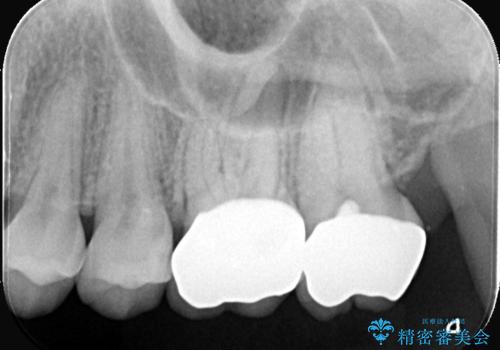

経過観察と土台作り: 一定期間の経過を観察し、痛みや炎症がないことを確認。神経の生存を確認した上で、セラミックを支えるための土台を精密に構築しました。

セラミックによる修復: 最終的な被せ物(または詰め物)にはセラミックを使用しました。高い適合性により、二次的な虫歯のリスクを抑えつつ、天然歯のような自然な咬み心地と美しさを再現しました。